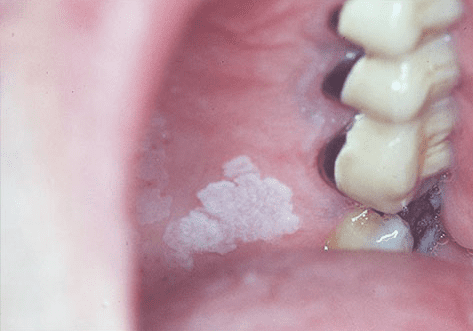

口腔白斑(Oral Leukoplakia)是指出現在口腔黏膜上的白色斑塊或斑片,無法通過擦拭去除,且並非其他已知疾病或病變所引起。世界衛生組織(WHO)將口腔白斑定義為「口腔黏膜上以白色為主的斑塊,不能臨床或病理學上診斷為其他任何疾病」。這種病變通常被認為是一種癌前病變,意味著它有潛在的惡性轉化風險。

口腔白斑可發生於口腔的任何部位,常見於頰黏膜、舌頭、牙齦和口腔底部。雖然大多數白斑是良性的,但約有3%至5%的病例可能發展為口腔鱗狀細胞癌,因此早期診斷和治療至關重要。

醫師首先會仔細檢查口腔,觀察白斑的位置、大小、形狀、顏色和質地。典型的口腔白斑表現為白色或灰白色斑塊,表面可能光滑或粗糙,邊界清楚或模糊。醫師還會評估是否有潰瘍、紅斑或硬結等可能提示惡性變化的特徵。

最典型的表現是口腔黏膜上出現白色或灰白色斑塊,這些斑塊:

- 無法通過擦拭去除

- 可能單發或多發

- 大小從幾毫米到幾厘米不等

- 表面可能光滑(均質型)或粗糙不平(非均質型)

- 均質型白斑:表面均勻白色,可能有細小皺紋